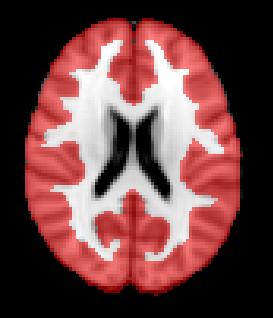

Advanced MRI biomarkers for MS progression

Changes in brainvolume are predictive of clinical and

disability status in CIS, RRMS, and PPMS

Spinal cord atrophy rates in patients with RRMS versus patients who transitioned to SPMS:

mm / year

Patients who developed SPMS showed accelerated spinal cord atrophy rates before conversion compared with their RRMS matches (p<0.0001)

This difference exists at least four years before the conversion to SPMS

Upper cervical cord atrophy, as assessed by MRI, is a predictor of the conversion to SPMS